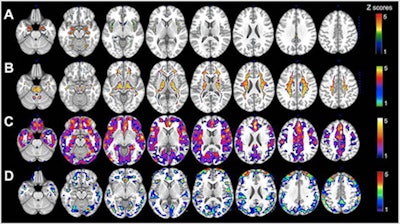

All participants underwent PET imaging with carbon-11-labeled Pittsburgh Compound B (PiB) to detect beta-amyloid protein, which is associated with the onset of Alzheimer's; FDG to determine the degree of neurodegeneration; and structural MRI to measure the brain's white and gray matter.

PET and MRI, respectively, revealed statistically significant differences (p < 0.05) between the genders in four categories. The women presented with the following:

- 30% more beta-amyloid plaques in women on average in the brain than men

- 22% less glucose metabolism, primarily in the superior frontal gyrus, medial frontal gyrus, and inferior parietal lobule

- 11% less gray matter volume (0.73 cm3) on average in women, compared with men (0.8 cm3)

- 11% less white matter volume (0.74 cm3) on average in women than men (0.82 cm3)